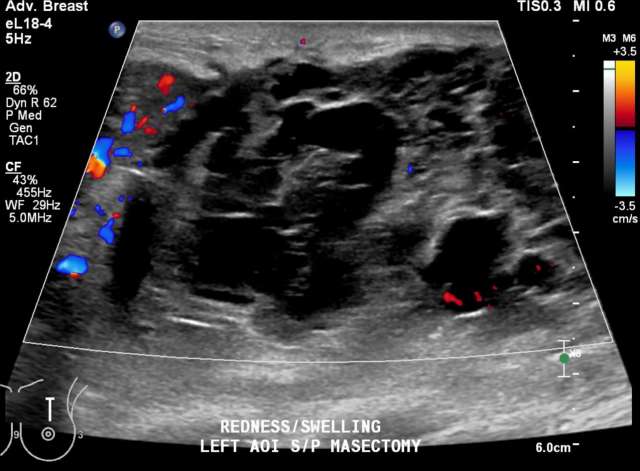

• US: Complicated hypoechoic or isoechoic fluid collection. Mobile debris within the fluid collection and hypervascularity of the adjacent breast tissue are characteristic, Figure 1.7

Case: Post-Surgical Fluid Collections Figure 1

Figure 1 - Ultrasound demonstrates septated, heterogenous fluid collection with surrounding hypervascularity. The patient was 3 weeks status post mastectomy and presented with breast redness and tenderness. The collection was drained, with cultures growing staph aureus.